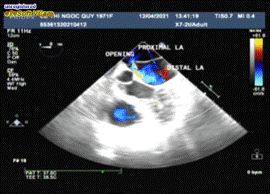

Echocardiography

Routine 2D Echocardiography visualized normal size of cardiac chambers with good LV systolic function (LVDd=43mm, LVEF=70%), absent pulmonary hypertension (systolic PAP=28mmHg). The apical views of 2D and 3D illustrated the membrane similar to diaphragm which divided the left atrium into two chambers: a proximal chamber that received the pulmonic veins and a distal chamber emptying into the mitral valve. The opening of membrane appeared as large type with 10mm in diameter, flow across the fenestration was present but not aliasing. The peak velocity of mitral flow was 0.89m/s in normal range. The peak velocity of flow across the membrane opening reached about 0.8m/s.

TEE visualized better the membrane and its anatomical relation on the most views as 0°, 45°, 60°, 90° and 135°.The thin membrane lied above the left atrial appendage on the 60° TEE image, the accessory atrial chamber received all pulmonary veins. Especially the 135° view demonstrated very clearly the site and size the of membranous opening, the fenestration located next to the ascending aorta and the anterior mitral leaflet and large with 11 mm in diameter. The images were obtained from 3D TEE also visualized the separated membrane with large opening (Figures 3-12).

Figure 3. Apic. 4C view showed a transverse linear membrane dividing the LA into 2 parts; the proximal acessory chamber received the PVs, the distal true LA openned to mitral orifice

Figure 5. xPlane apical views illustrated the laminal color flow across the opening

Figure 6. color live 3D imaging showed the dividing membrane and flow across the fenestration .

Echocardiography is the first clue to detect cor triatriatum sinister, the undulating membrane may be seen on parasternal long, short axis, but better visualized on apical 2 and 4- chamber views, especially when xPlane mode is used. Two dimensional echocardiography and Doppler imaging illustrate the size and location of fenestration and the degree of obstruction including laminal or turbulent flow, velocity of flow across the membranous orifice.

Transesophageal echocardiographic 450, 600 and 900 views define the relationship between the membrane and the LAA, then allow differentition from supramitral ring. The 600 view of this patient demonstrated LAA locating inferior to the membrane, this anatomical finding confirmed the diagnosis of cor triatriatum. Transesophageal echocardiogrphy can be useful to detect associated lesions as ASD, VSD, anormalous pulmonary veinous return. Combined 2D TTE and 2D TEE are often the initial imaging modalities of choice when assessing anatomy and physiology in this congenital defect, adjunctive 3D TEE may improve the diagnosis of cor triatriatum and visualization of the culprit membrane in the way not possible by standard 2D imaging15.

Transesophageal  echocardiography 1350 view in this case was the best one to visualize the undulating  membrane that attached to the LA wall and leaved a large opening with non-accelerated laminal flow. 3D TEE is a more recent diagnostic tool providing additional information, able to demonstrate the entire membrane, the size, the location and the number of openings in the dividing membrane. Righab Hamdan et al. reported the crescent shape of the membrane view from the pulmonary veins on 3D TEE in a patient with obstructive cor triatriatum sinister associated with atrial flutter and secundum atrial septal defect.